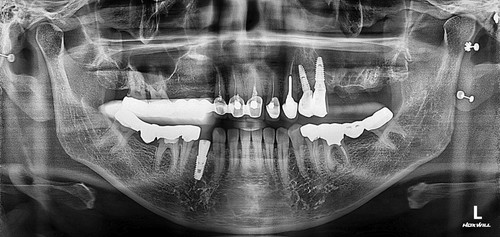

상악동누공폐쇄술이 성공하면 그 다음 단계로는 치조골 이식과 임플란트 식립을 해야 하는데 간혹가다 일반적인 상악동거상술에 비하면 누공이 있었던 부위는 상악동점막과 잇몸살이 유착되어서 힘든 경우가 많습니다. 물론 폐쇄술을 시행하면서 상악동에 뼈이식을 동시에 하는 것도 하나의 방법이 될수 있겠으나 성공했을 때 뿐만 아니라 누공폐쇄술이 실패했을 때를 가정한다면 통상적으로 동시 뼈이식을 시행하기에는 다소 위험성이 따르는 것이 사실입니다. 그래서 이 환자분은 안전하게 단계적으로 진행하기로 하였으며 누공폐쇄술이 성공한 후에 상악동 측방거상술을 시행하였고 이식한 뼈가 충분히 굳은 후에 임플란트를 식립하였습니다.

임플란트를 식립한 후에는 통상적으로는 3개월 후에 임플란트 보철물이 들어가는데 환자분의 사정으로 치과 내원을 못 하셔서 약 5개월 후에 오셨는데 왼쪽 아래 치아의 뿌리 부위의 충치가 발견되어서 아래 치아는 발치하면서 식립하는 즉시식립을 해 드렸습니다.

보통 하악에 임플란트 식립하면 2개월 이내에 치아가 들어가는데 마찬가지로 환자분 사정으로 못 오시다가 6개월이 지나서야 위,아래 임플란트 머리가 들어가고 마무리 할수 있었습니다.